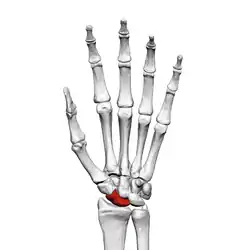

![]() Ліва рука спереду (з боку долоні). Човноподібна кістка виділена червоним. | |